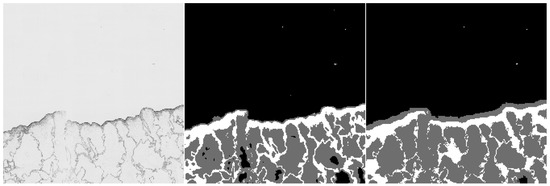

Furthermore, we provide examples of qualitative results comparing both methods. Figure 6 and Figure 7 show the results, where the UNet-Mini corrected or partially corrected the original mistakes in labels. On the other hand, an example of obvious mislabels made by the network can be found in Figure 8. Finally, Figure 9 provides an example of equally good results from both tested methods.

Figure 6. Example of semantic segmentation, where the neural network reached better results. The original image (on the left), the result from the HCTFS (in the middle), and the results from the neural network (on the right).

Figure 7. Example of semantic segmentation, where the neural network reached better results. The original image (on the left), the result from the HCTFS (in the middle), and the results from the neural network (on the right).